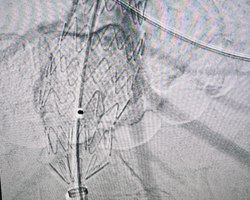

В Региональном сосудистом центре Областной больницы впервые выполнено эндопротезирование брюшной аорты.

Эндопротезирование брюшного отдела аорты — это инновационная малотравматичная методика, которая позволяет:

Операция выполнена руководителем центра Андреем Куликовым, заведующим отделением сосудистой хирургии Игорем Гладковым, заведующим отделением рентгенхирургических методов лечения и диагностики Андреем Колуновым и врачами отделения сосудистой хирургии.